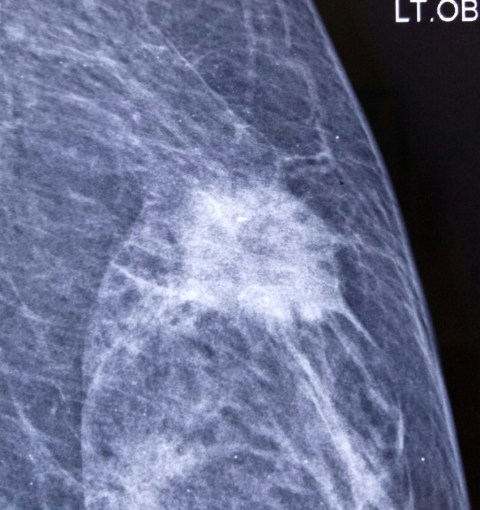

MRM for breast cancer, with PET scan showing axillary mets. 45 years old, c/o dr Jasleen.

5.1.19